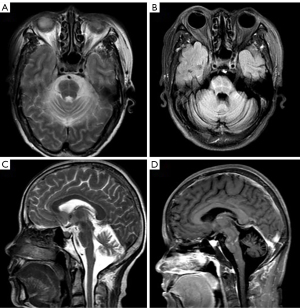

A 56-year-old Chinese woman was admitted to Binyang Hospital for a 13-month history of progressive ataxia found by her family. The initial symptom was gait instability in March 2020. After 1 month, she could not have dinner with chopsticks accurately and engage in the manual work that she used to do, such as carrying heavy objects. She developed dysarthria 2 months later. At her local hospital, the diagnosis of ataxia related to hypothyroidism was given and a replacement therapy with levothyroxine was started. This treatment had no effect on her ataxia. Her ataxia worsened gradually. In June 2021, a magnetic resonance imaging (MRI) of the brain was done. It showed a cerebellar ataxia and a Hot Cross Buns (HCB) sign in T2-weighted (T2W) images in the pons as shown in Figure 1. The initial diagnosis of cerebellar subtype of multiple system atrophy (MSA) was considered. Family history of ataxia was negative. Neurological examinations showed a cerebellar syndrome with wide base gait, bilateral gaze horizontal nystagmus, mild right eyelid ptosis and dysarthria, dysmetria on finger-nose and heel-to-knee tests, and a positive Romberg sign. Her orientation, cognitive function, strength, deep-tendon reflexes, deep sensory and plantar reflexes were all normal. She did not describe any autonomic symptoms and suffer from any other symptom of unexplained autonomic dysfunctions such as voiding difficulties with post-void urinary residual volume ≥100 mL, urinary urge incontinence, neurogenic orthostatic hypotension (≥20/10 mmHg blood pressure drop) within 3 minutes of standing, or head-up tilt test (4).